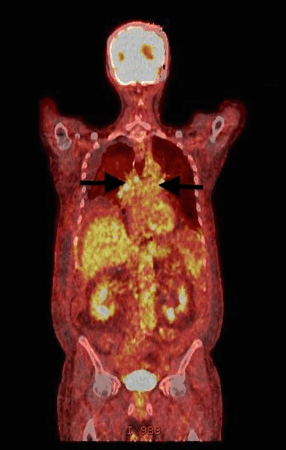

A 67-year-old Caucasian male with past medical history of hypogonadism, hyperlipidemia, depressive mood disorder, chronic obstructive pulmonary disease, type 2 diabetes mellitus, coronary artery disease and hypothyroidism presented with a one year history of weight loss of approximately 20 pounds. Laboratory analysis was significant for transaminitis, with alanine transaminase and aspartate transaminase both >200 IU, alkaline phosphatase >1200 IU, total bilirubin 7 mg/dl, direct bilirubin 5 mg/dl, albumin 2 mg/dl. Diagnostic imaging revealed CT abdomen and pelvis with new significant extra and intrahepatic biliary ductal dilatation associated with abrupt narrowing of the distal common bile duct at the level of the pancreatic head. There was radiographic evidence of pancreatic ductal dilatation that appeared chronic in nature. There was slight interval increase in fullness of the pancreatic head compared a previous study published four years prior. Additionally, there was a questionable soft tissue density that projected into the second part of the duodenum, suspicious for neoplasm of the pancreatic head. Lastly, there was interval increase in peripancreatic and retroperitoneal lymphadenopathy. An ERCP with biopsy was performed, and histopathologic analysis demonstrated mucinous carcinoma of the pancreas. The patient's hospital course was complicated by acute cholangitis and pancreatitis deemed secondary to the endoscopic intervention into the biliary system. A subsequent PET scan of the chest revealed hilar and mediastinal lymphadenopathy (Figure 1). The patient was eventually stabilized and referred for hospice care. A few months later he expired as a result of complications from pancreatic adenocarcinoma. An autopsy was requested by the family, which revealed non-caseating granulomatous inflammation of the hilar and mediastinal lymph nodes consistent with sarcoidosis.

Figure 1: A PET scan showing highlighted enlarged mediastinal lymph nodes (black arrow).